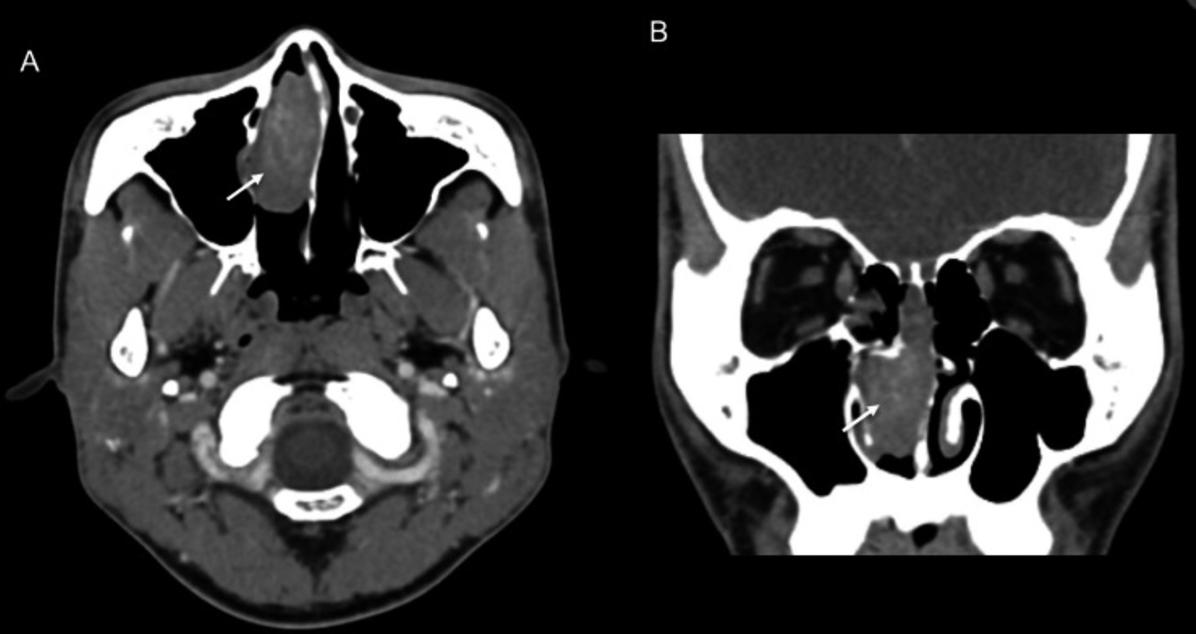

鼻窦CT提示一4.0cm*2.1cm*3.8cm肿物,向上延伸至鼻顶,右中鼻甲移位,中鼻道闭塞,鼻中隔向左侧偏曲。鼻中隔中部可见轻微骨质侵蚀(图2)。窦腔内未见明显占位。

图2